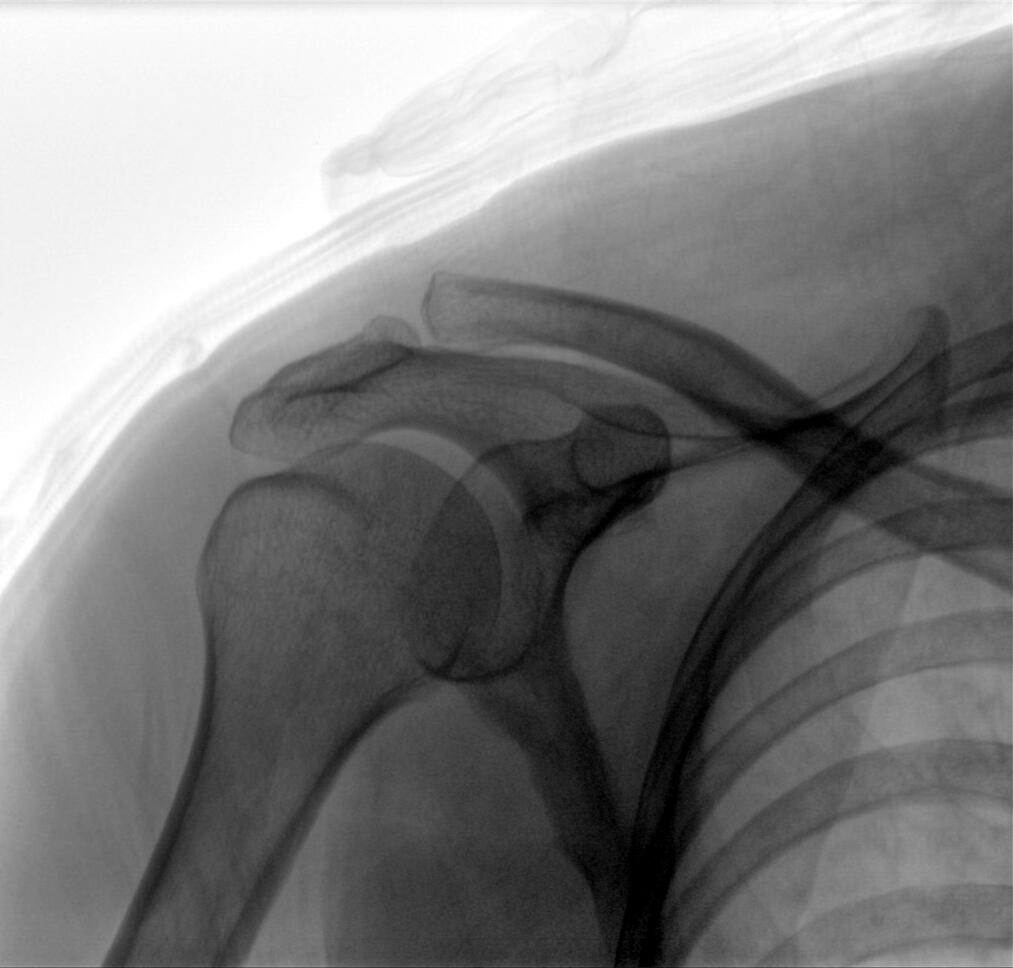

Clinical picture

臨床圖片